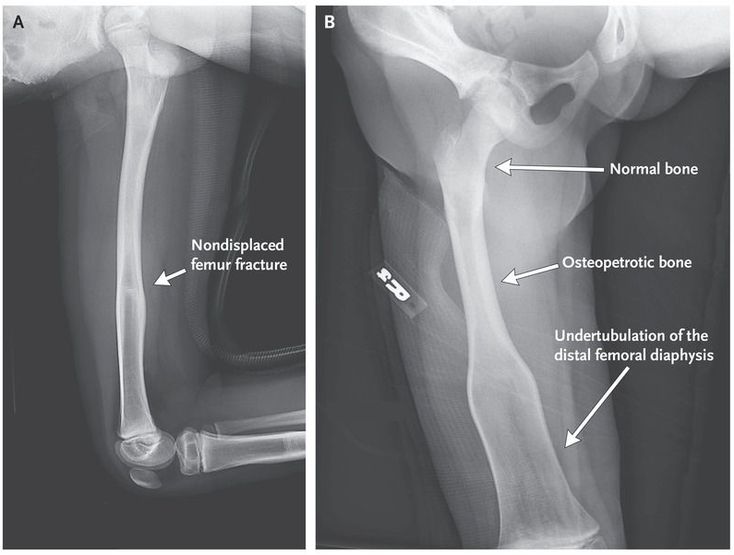

An 8-year-old boy presented with new-onset acute pain in his right leg. Radiographs showed a nondisplaced fracture (Panel A) and undertubulation of the distal femoral diaphysis — a condition known as Erlenmeyer-flask deformity (Panel B). He had a history of neuroblastoma, which was diagnosed when he was 6 months of age; the disease progressed after standard chemotherapy but had been in remission for the 5 years before this presentation, after treatment with cyclophosphamide and monthly intravenous bisphosphonate therapy. Bisphosphonate therapy was discontinued after 18 months because of concern about osteopetrosis on routine radiographic imaging. Laboratory testing, imaging, and genetic testing did not reveal any hereditary or other common causes of acquired bone disease, including primary bone marrow disorders, heavy-metal poisoning, bone metabolic diseases, and other dysplasias. The delineation between osteopetrotic and normal bone (Panel B) suggested a period of increased bone turnover followed by improved bone growth. This finding is more consistent with bisphosphonate exposure than with an underlying genetic condition. The patient remains at risk for fractures in transition areas between osteopetrotic and normal bone. It was recommended that he avoid contact sports and continue annual follow-up; 18 months later, he has had no new symptoms or fractures.